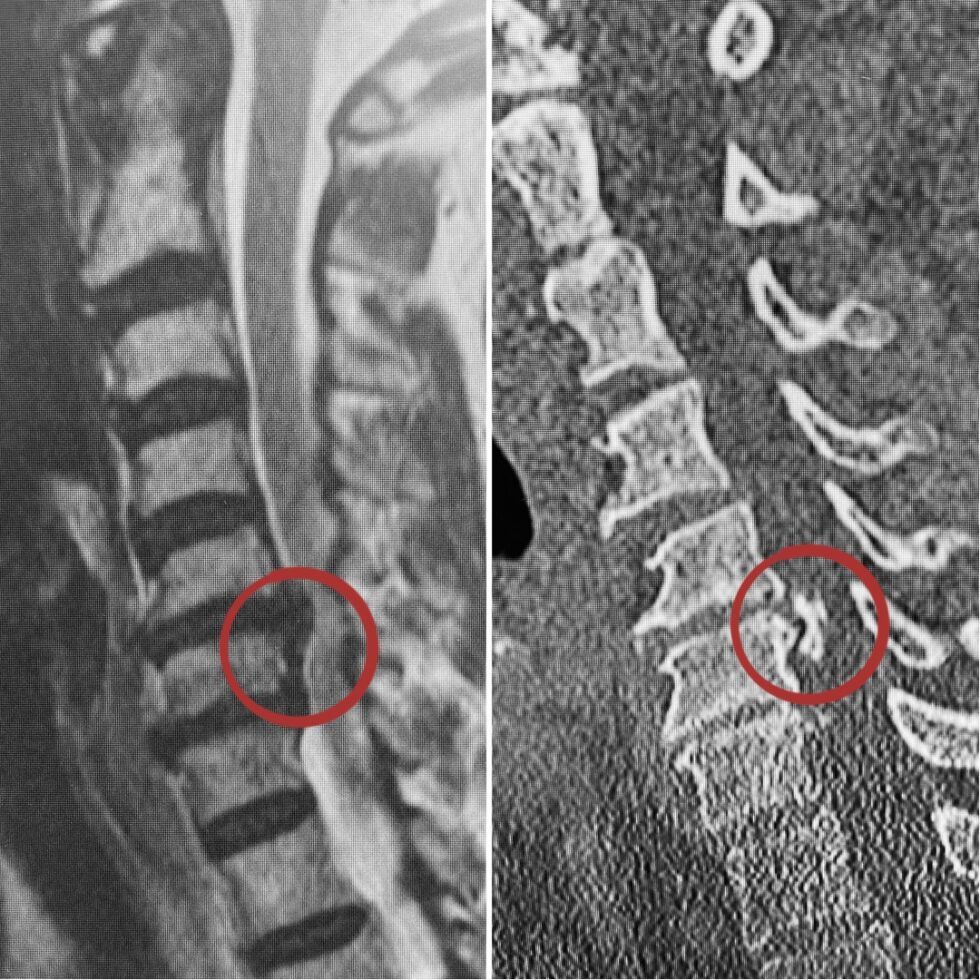

Ligamento Longitudinal Posterior . Web ossification of the posterior longitudinal ligament (opll) refers to bone formation within the posterior longitudinal. Web the posterior longitudinal ligament (pll) runs within the vertebral canal, along the posterior surface of the vertebral bodies between the axis (c2 vertebra) and.

Web the posterior longitudinal ligament runs in the spinal canal attaching to the vertebral bodies and vertebral discs and tightens with cervical flexion. Web ossification of the posterior longitudinal ligament (opll) refers to bone formation within the posterior longitudinal. Web the posterior longitudinal ligament is situated within the vertebral canal, and extends along the posterior surfaces of the bodies of the.

Ligamento Longitudinal Posterior - Web what is the posterior longitudinal ligament (pll)? The pll is a sturdy ligament located within the spinal. Web ossification of the posterior longitudinal ligament (opll) refers to bone formation within the posterior longitudinal. Web the posterior longitudinal ligament (pll) is a band of collagen and elastin fibers that extends along a line along the posterior margins of the vertebral.

Ligamento Longitudinal Posterior - Web ossification of the posterior longitudinal ligament (opll) refers to bone formation within the posterior longitudinal. Web the posterior longitudinal ligament (pll) is a band of collagen and elastin fibers that extends along a line along the posterior margins of the vertebral bodies from the. Web the posterior longitudinal ligament is one of the three more important. Web the posterior.

Ligamento Longitudinal Posterior - Web ossification of the posterior longitudinal ligament (opll) refers to bone formation within the posterior longitudinal. Web the posterior longitudinal ligament runs in the spinal canal attaching to the vertebral bodies and vertebral discs and tightens with cervical flexion. Web the posterior longitudinal ligament (pll) is a band of collagen and elastin fibers that extends along a line along the.